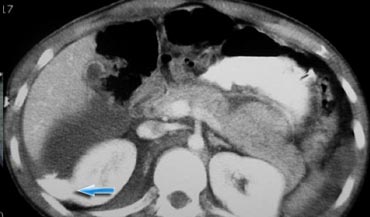

Hãy quan sát các hình ảnh bên trái và cố gắng trả lời các câu hỏi sau:

- Vai trò của CT ở bệnh nhân chấn thương xuyên thấu là gì?

- Các dấu hiệu hình ảnh là gì?

Đáp án:

- Vai trò chính của CT là xác định xem có vi phạm phúc mạc hay không và dự đoán nhu cầu phẫu thuật mở bụng

-

Các dấu hiệu hình ảnh:

Trong pha mạch máu ở phút thứ 1, có hiện tượng thoát thuốc cản quang và dịch trong các rãnh cạnh đại tràng, cho thấy vi phạm phúc mạc.

Ngoài ra còn có khối máu tụ trong khoang quanh thận. - Trong pha muộn, có thêm hiện tượng thoát thuốc cản quang, mặc dù chưa rõ liệu đó là do chảy máu tích cực hay thuốc cản quang thoát ra từ hệ thống thu thập nước tiểu

- Trong pha bài tiết, rõ ràng có sự vi phạm hệ thống thu thập nước tiểu